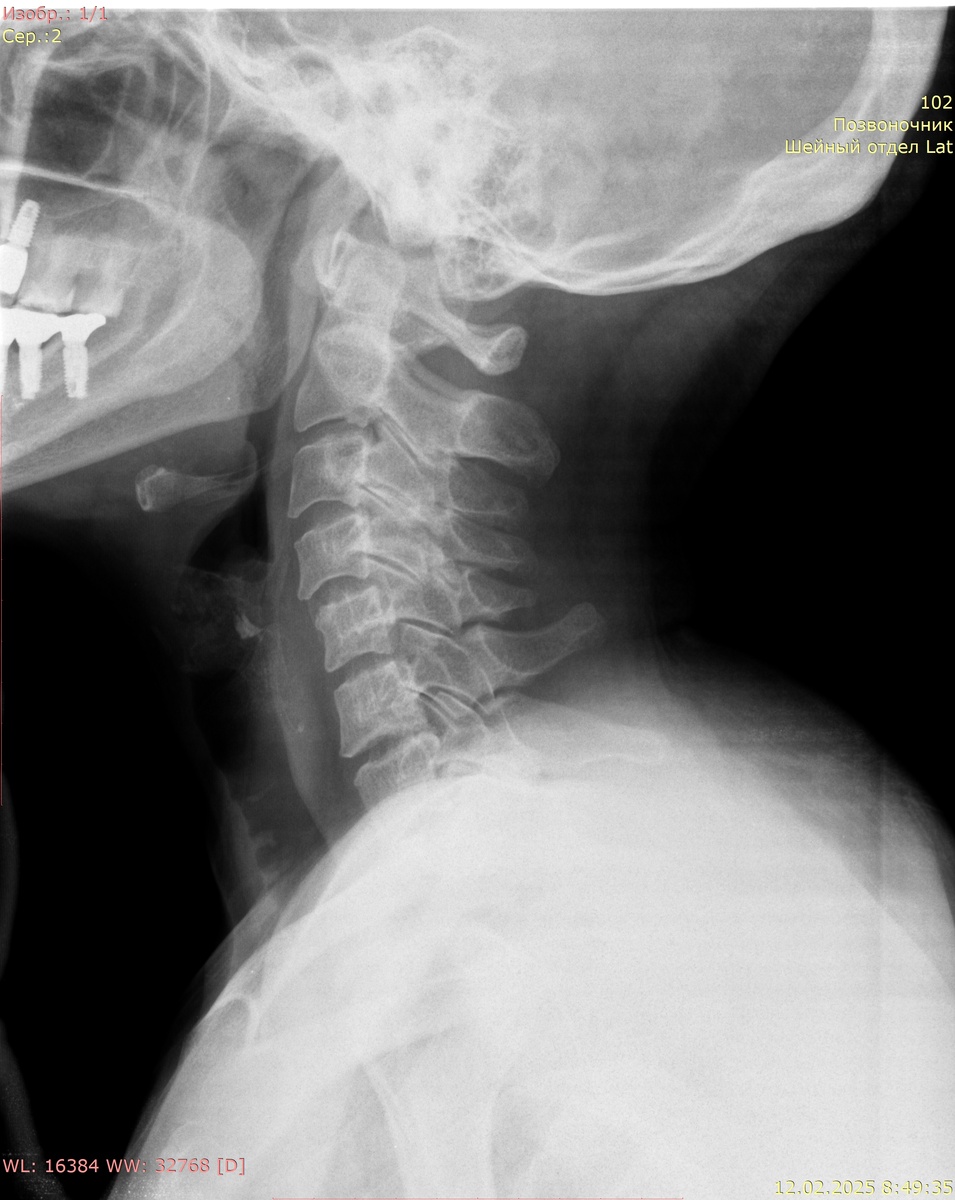

Цифровая рентгенография шейного отдела позвоночника, функциональное исследование в боковой проекции в положении сгибания и разгибания:

Соотношение позвонков правильное. Сгибание и разгибание недостаточное. В положении сгибания и разгибания отмечается смещение С4 кпереди на 4.5 мм.

Заключение: антелистез С4 1 степени. Дегенеративно-дистрофические изменения шейного отдела позвоночника.